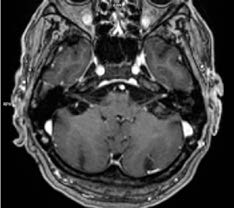

Realiza ressonância magnética crânio encefálica (RM-CE) e de ouvido com injeção de gadolínio, que evidencia realce patológico dos nervos facial, glossofaríngeo e vago esquerdos, de provável natureza inflamatória/infeciosa. Admite-se muito incipiente realce do nervo vestíbulo-coclear esquerdo. Preenchimento da cavidade otomastoideia esquerda, associando-se algum realce dos tecidos moles do ouvido externo esquerdo, de provável natureza inflamatória / infeciosa, cuja ilustração se apresenta nas Figs. 1 e 2.